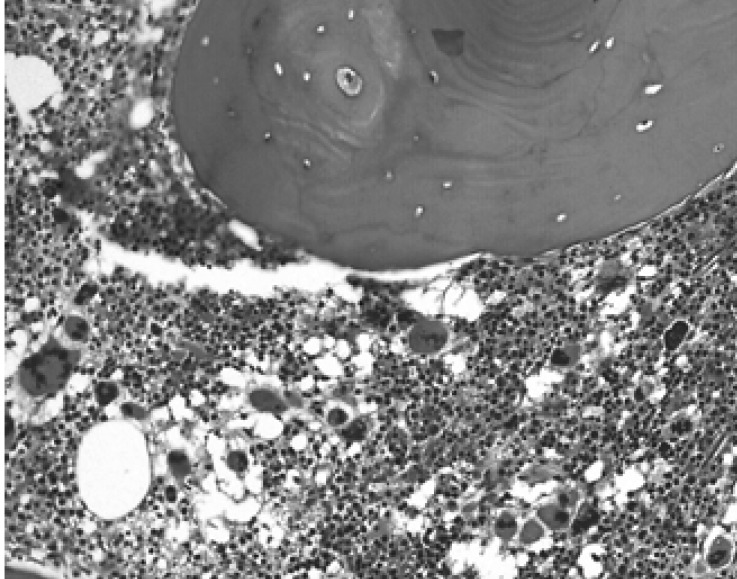

Figure 1

Bone marrow biopsy. Abundant number of megakaryocytes with atypical forms is shown, consistent with the diagnosis of essential thrombocythemia (H&E stain, ×200).